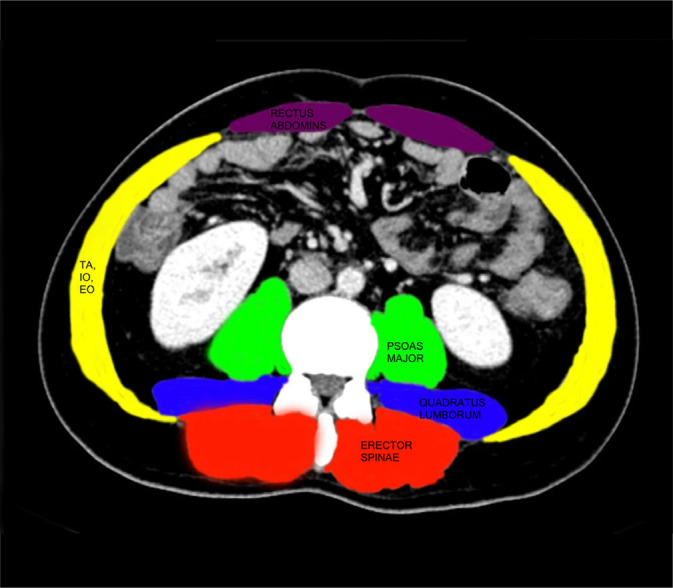

Material and methods: This prospective observational study was conducted at a tertiary liver transplant center between September 2023 and May 2024. USG was used to measure the thickness of the external oblique (EO), internal oblique, and transversus abdominis (TA) muscles in 41 liver transplant recipients and 41 healthy donors. Sarcopenia was also assessed using CT-based L3 skeletal muscle index (L3-SMI) and hand grip strength. Correlations with disease severity (Model for End-Stage Liver Disease, Child-Turcotte-Pugh (CTP)), postoperative outcomes, and ascitic fluid volume were analyzed.

Results: Abdominal muscle thickness was significantly lower in recipients compared to donors (EO: 2.9 ± 1.0 mm vs. 4.5 ± 1.8 mm; TA: 2.2 ± 0.7 mm vs. 3.2 ± 1.0 mm; p <0.001). Sarcopenia prevalence was 78% by L3-SMI and 82.9% by hand grip strength. ROC analysis demonstrated that EO <3.6 mm and TA <2.55 mm predicted sarcopenia in males with high sensitivity and specificity. Muscle thinning correlated with higher CTP scores, greater ascitic fluid volume, and prolonged intensive care unit stay.

Conclusions: USG-derived abdominal muscle thickness, especially EO <3.6 mm and TA <2.55 mm in males, is a reliable, non-invasive marker for sarcopenia in liver transplant candidates. It correlates with disease severity and postoperative morbidity, supporting its utility in pre-transplant risk stratification.